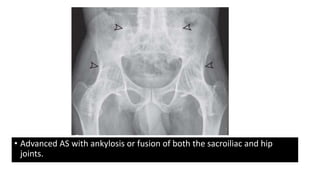

• Advanced AS with ankylosis or fusion of both the sacroiliac and hip

joints.

• Advanced ASwith ankylosis or fusion of both the sacroiliac and hip joints.